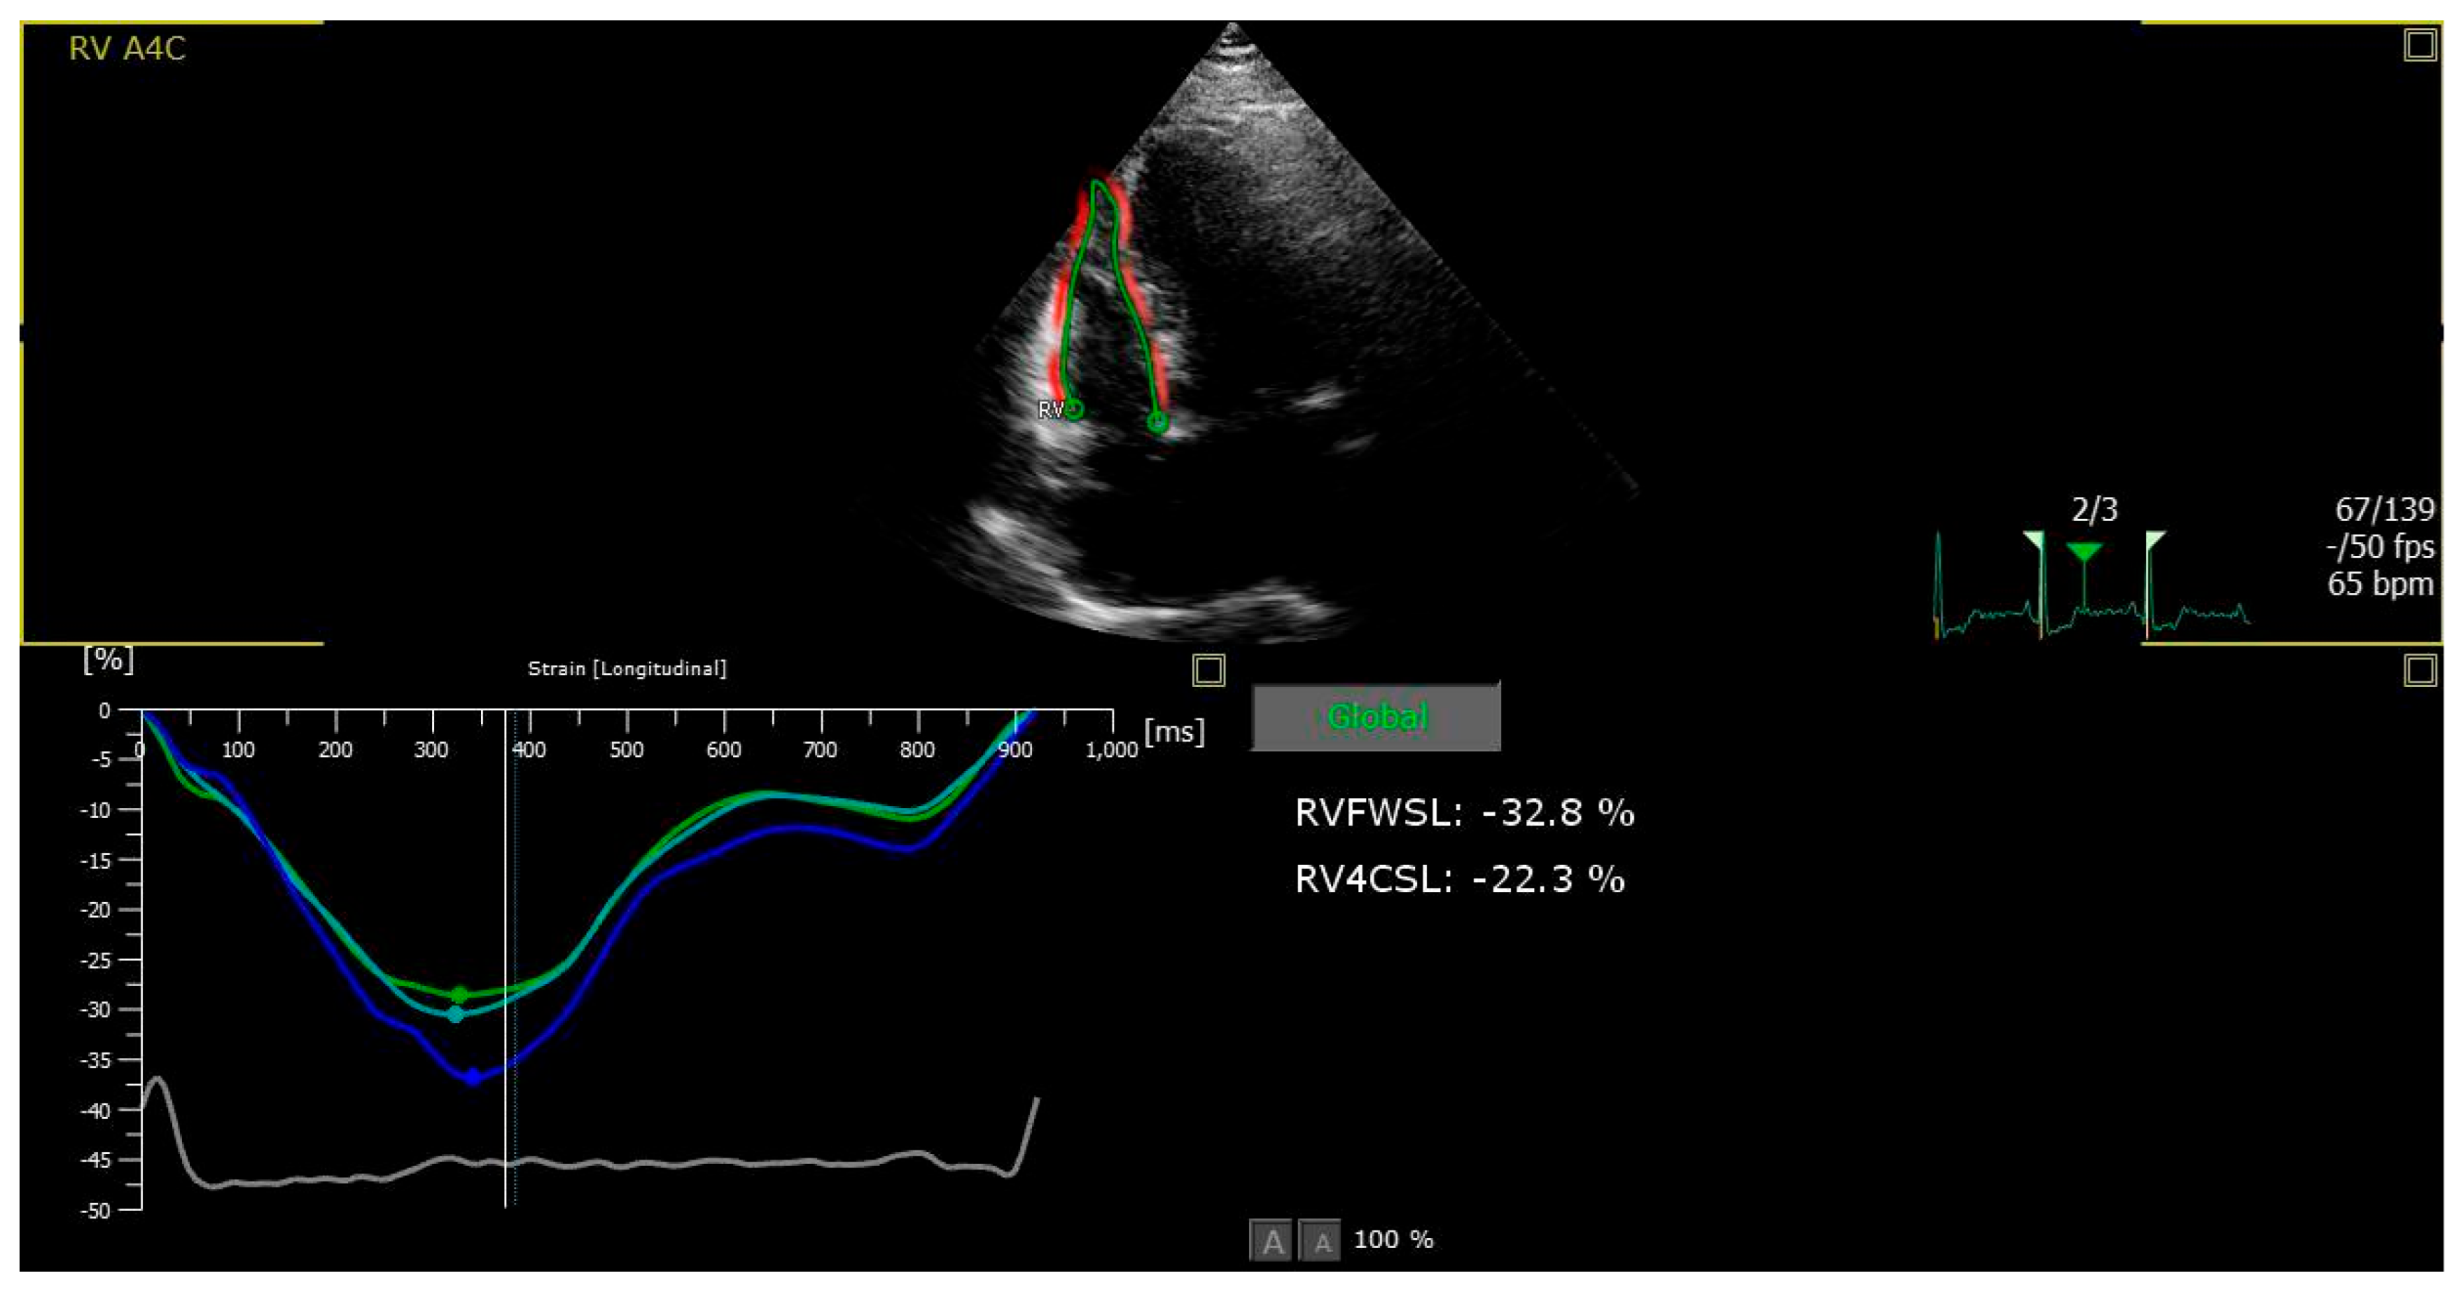

2.3. Speckle-Tracking Echocardiography: A Sensitive Index of RV Systolic Function

- Muraru, D.; Haugaa, K.; Donal, E.; Stankovic, I.; Voigt, J.U.; E Petersen, S.; A Popescu, B.; Marwick, T. Right ventricular longitudinal strain in the clinical routine: A state-of-the-art review. Eur. Heart J. Cardiovasc. Imaging 2022, 23, 898–912. [Google Scholar] [CrossRef]

- Lee, J.H.; Park, J.H. Strain Analysis of the Right Ventricle Using Two-dimensional Echocardiography. J. Cardiovasc. Imaging 2018, 26, 111–124. [Google Scholar] [CrossRef]